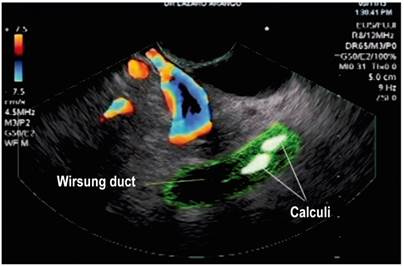

Dilation of the Wirsung duct or stones within this duct (Figure 2)

Figure 2 Dilation of the Wirsung duct and calculi within it, seen with Fujinon’s linear endosonography (image courtesy of the Union of Surgeons SAS, Lázaro Arango).